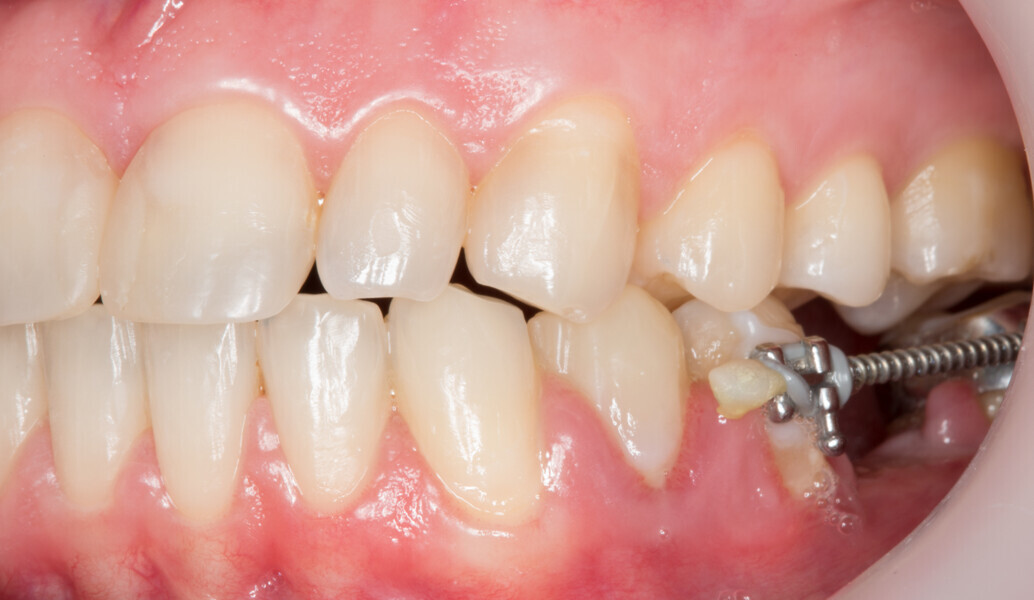

Fig. 2: Initial clinical situation.